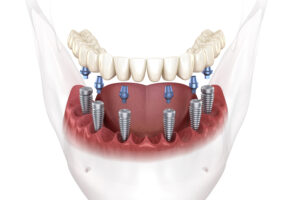

All-on-6 zubni implantati – prednosti i moguće mane

април 2, 2025

All-on-4 zubni implantati – prednosti i moguće mane